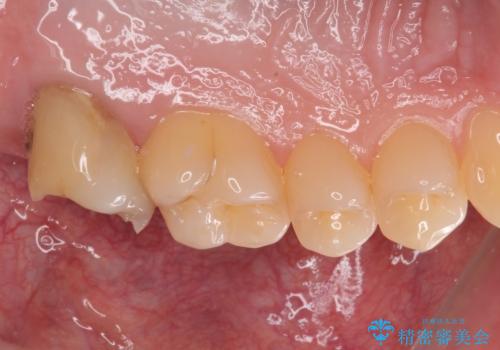

インプラントの埋入から被せものの装着まで2ヶ月で終えることができました。治療期間も短く、しっかり咬めるため大変喜んでいただきました。